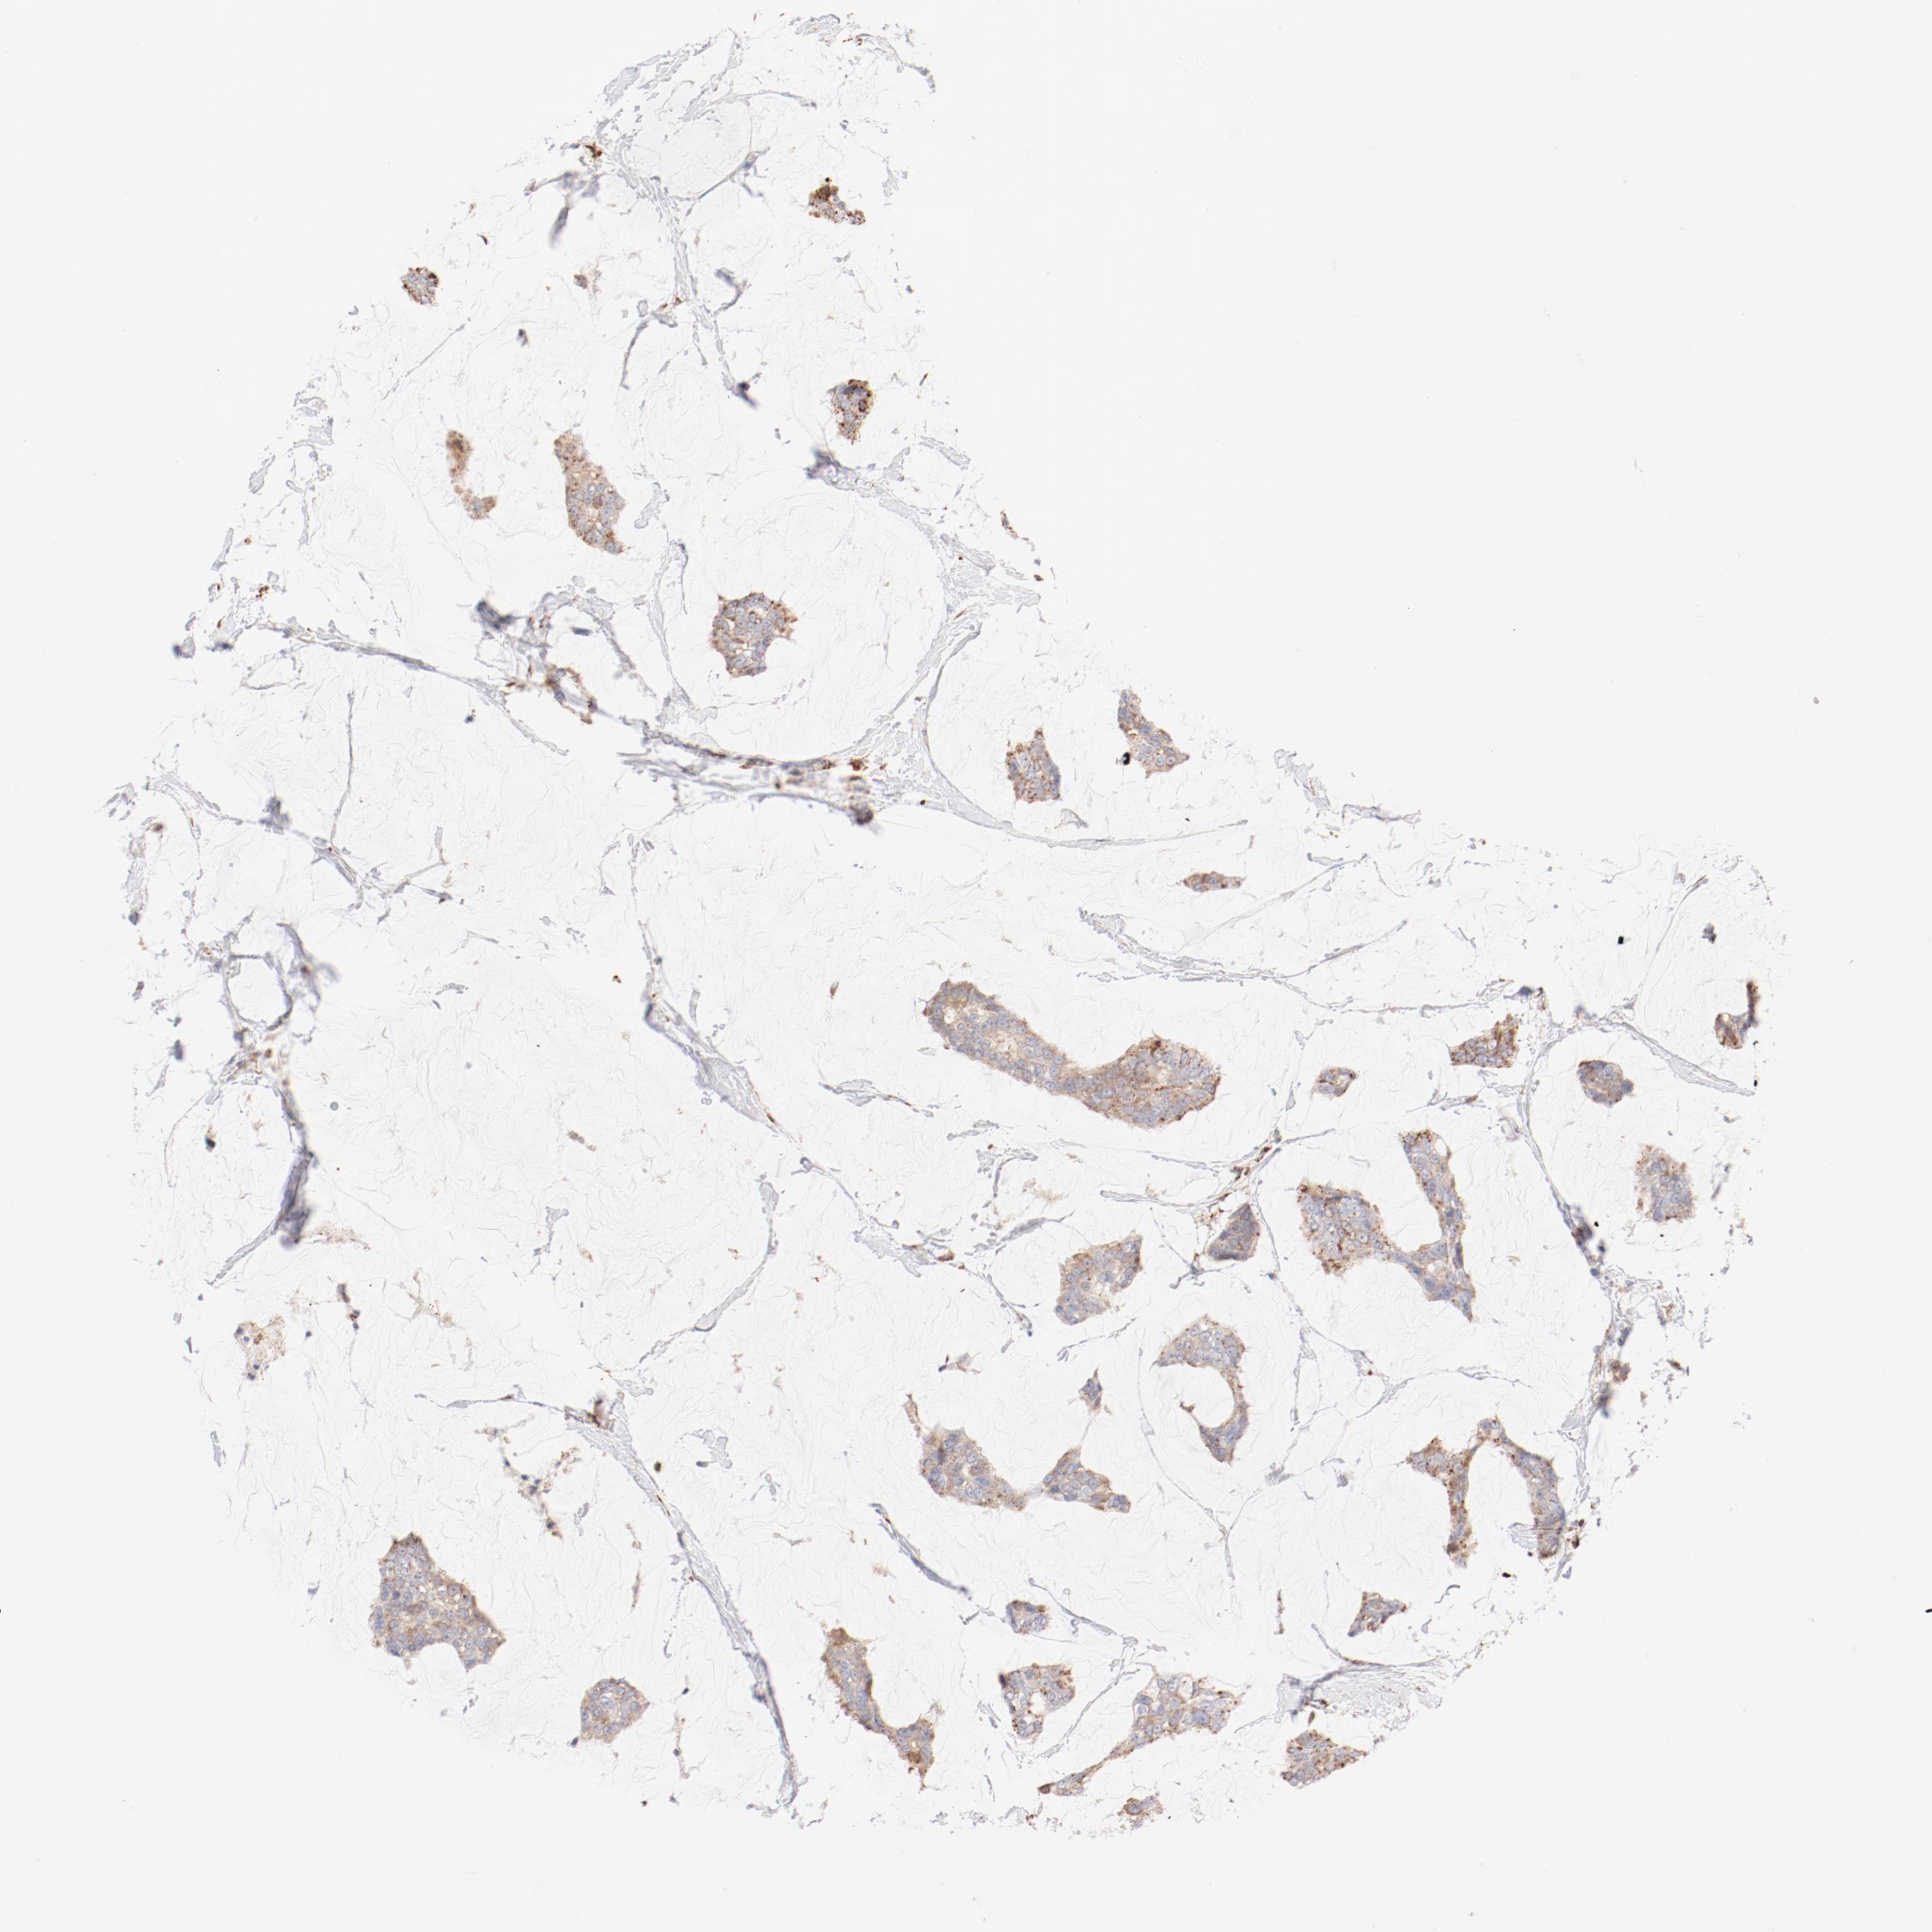

BRCA TCGA BRCA VALIDATION PROTEIN EXPRESSION

ANTIBODIES

AND

VALIDATION